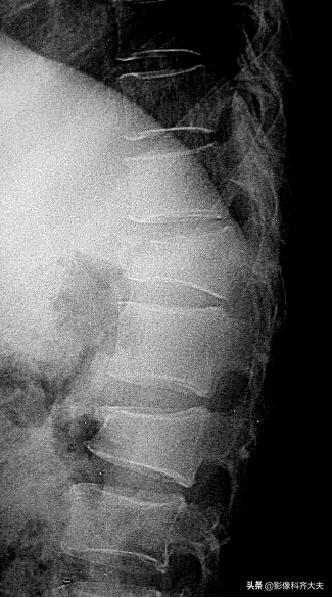

脊柱骨折

多数发生在青壮年,绝大多数都是间接外力所致,直接*力暴**多见于战伤、地震伤,另外肌肉的强力收缩(如破伤风或癫痫)亦可引起。

一般X线平片即可诊断

为了判定有无附件骨折及骨折片进入椎管内的位置需做CT检查,对骨折后脊髓改变的观察需做MRI检查。

X线平片:

可单个发生或多个椎体同时发生。

受累椎体可出现压缩骨折、楔形压缩骨折并椎体前缘游离骨块、前上缘与上位椎体下缘套叠骨折、纵行骨折等形态。

除形态改变外椎体松质小梁骨折嵌入,密度相对较高,表现为椎体面下0.1~1cm或在椎体中部的致密带状影,边缘较模糊。

胸12及腰2楔状变形,胸12椎体前缘可见碎骨片

椎体压缩骨折常合并上下关节突、横突、椎弓根及棘突骨折,一般X线平片正侧位可观察清楚。